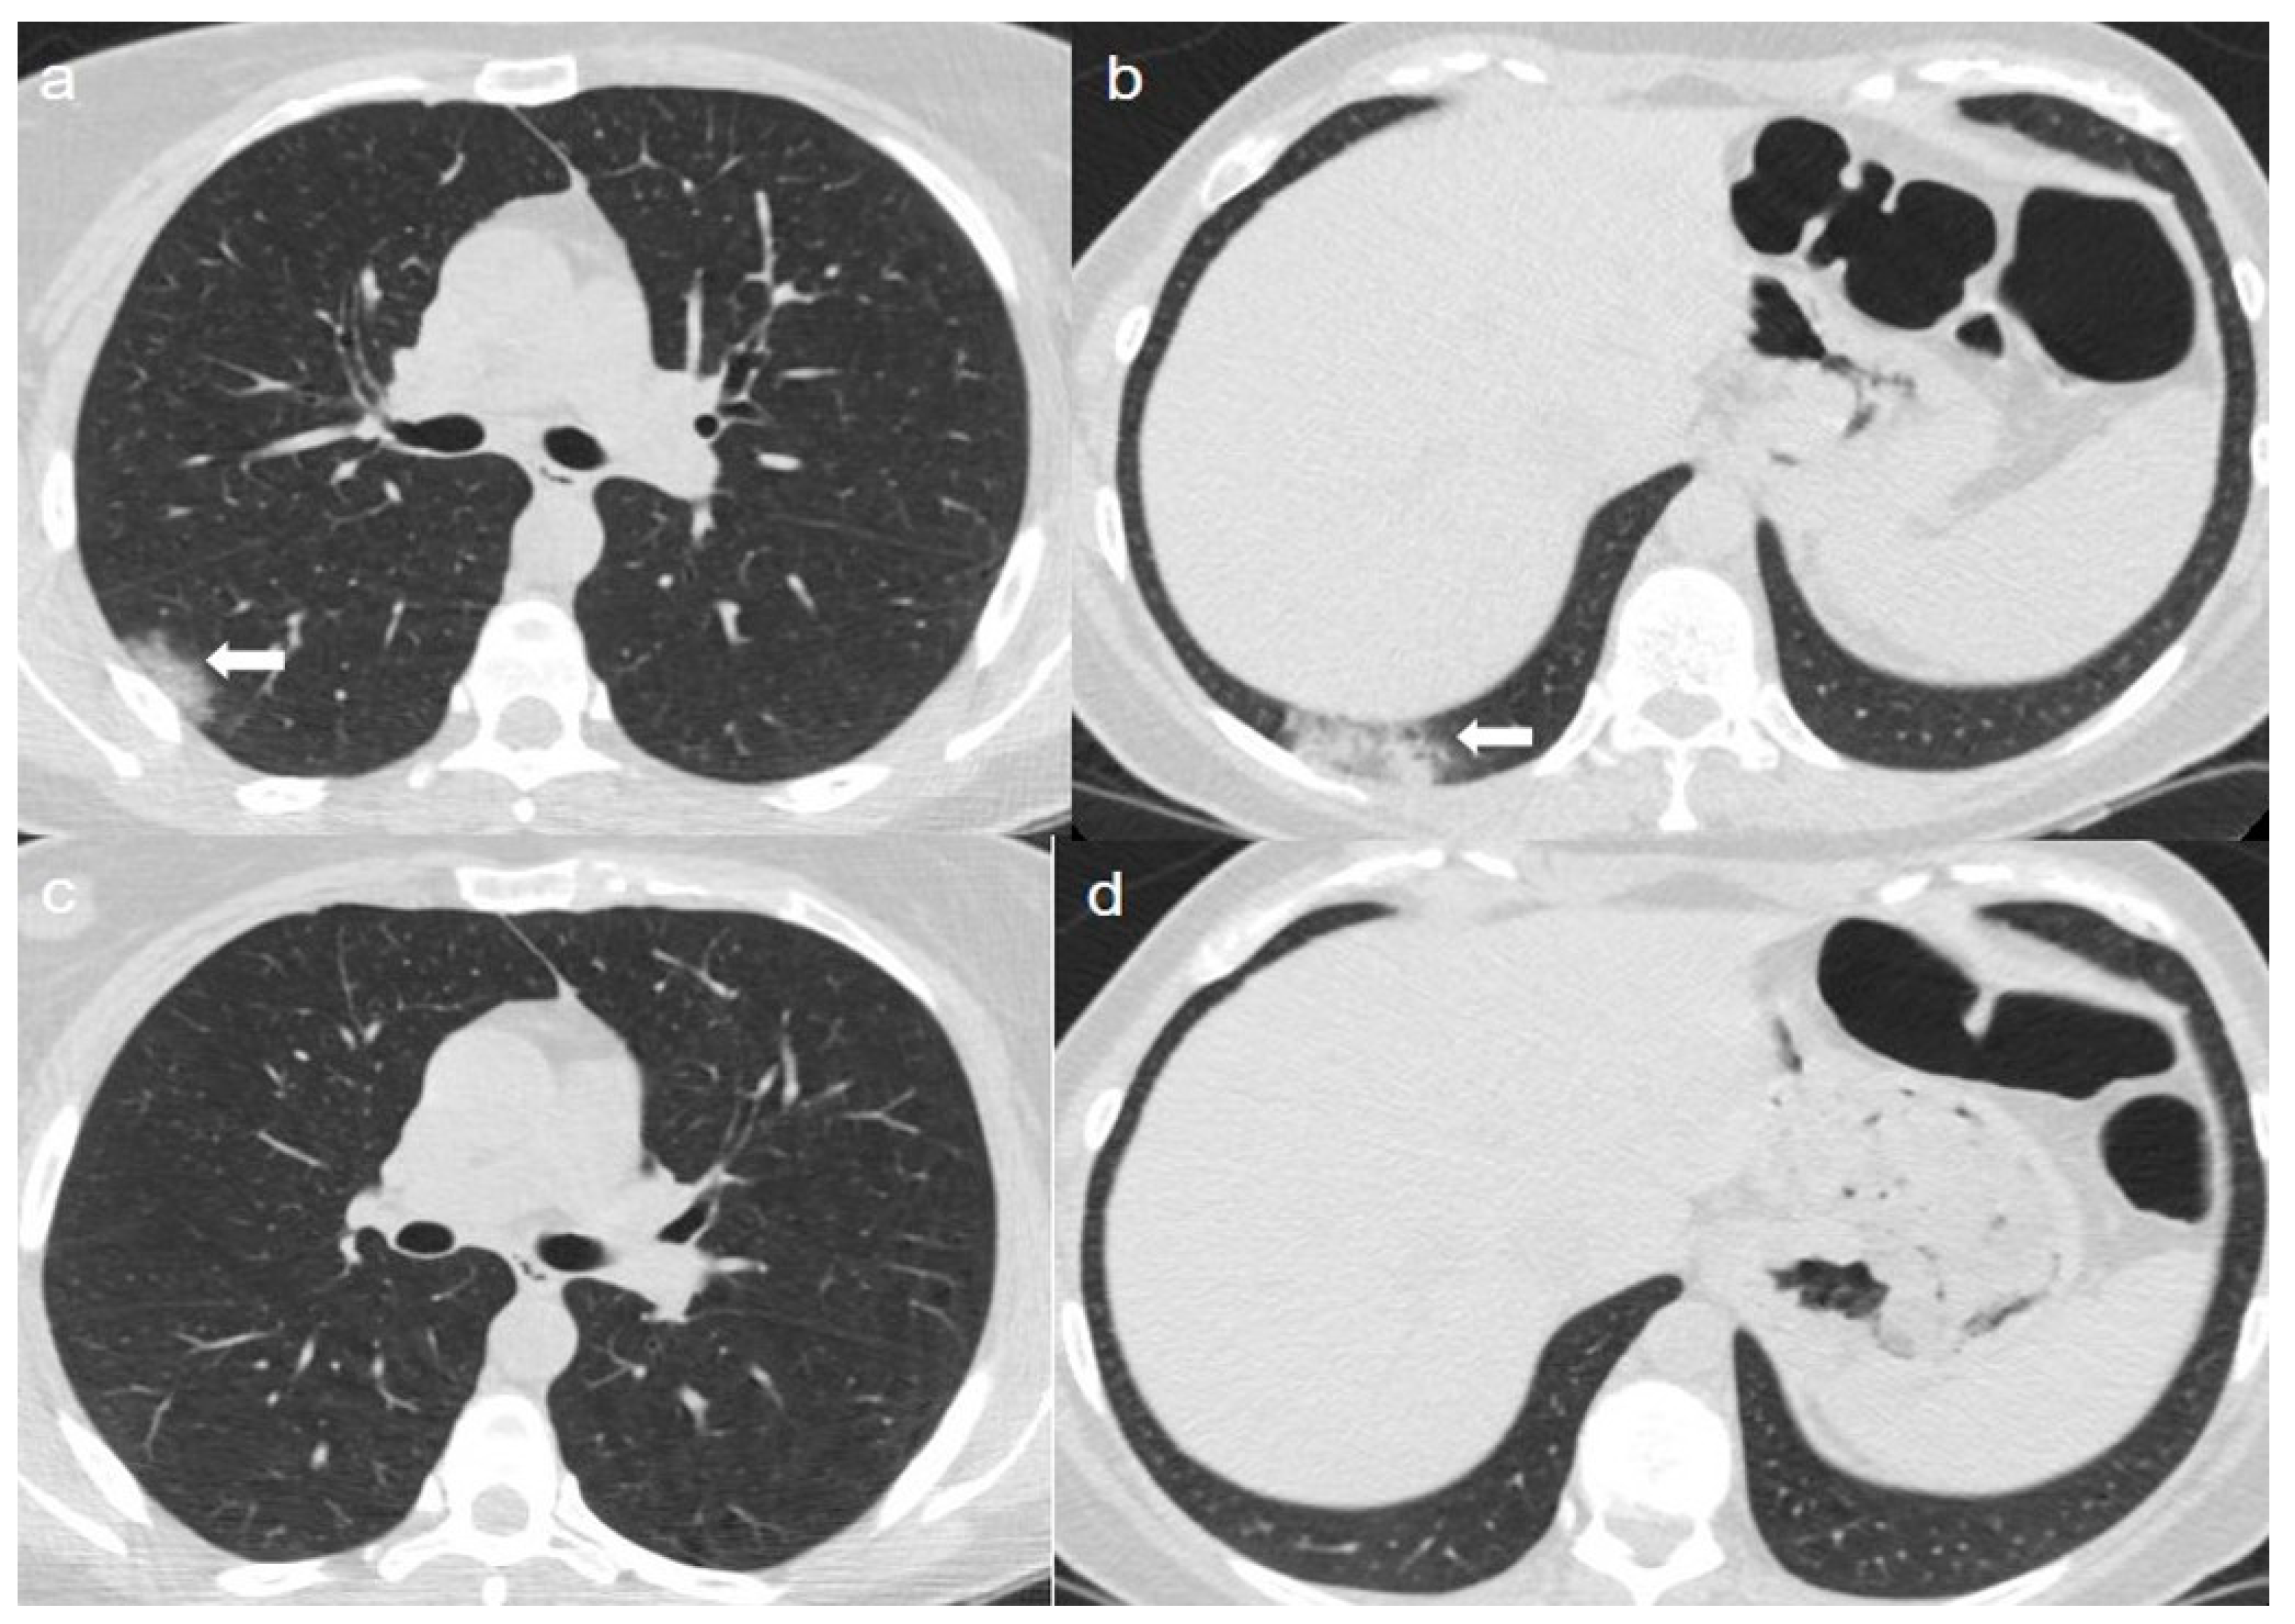

From pubs.rsna.org

CoronavirusHKU1 Pneumonia and Differential Diagnosis with COVID19 Case Report Covid Pneumonia this case report aims to alert healthcare workers on less common forms of presentation, and to introduce this. A report of 8 cases. presentation of case. in this case report, we aimed to assess clinical improvement following administration of intravenous tocilizumab. Case Report Covid Pneumonia.